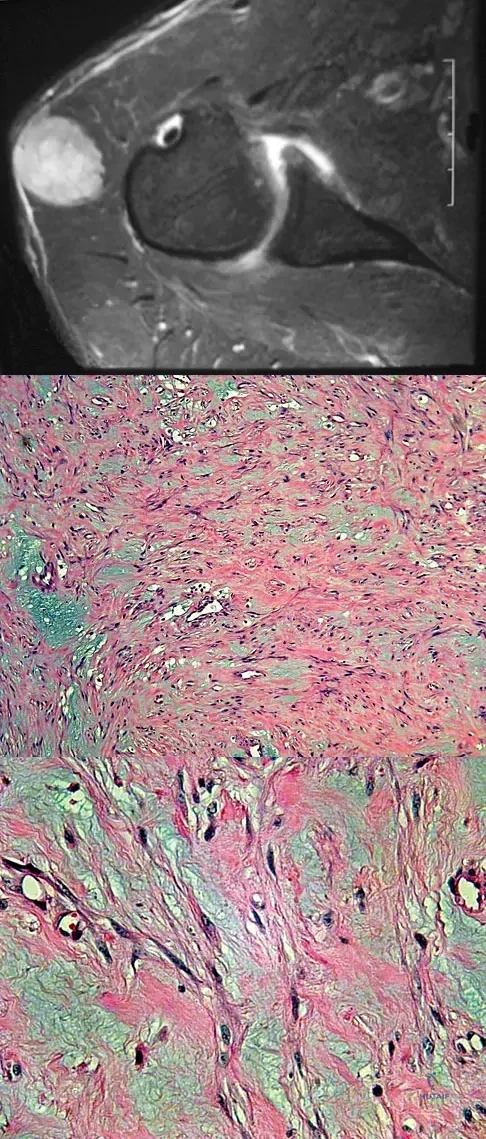

A 37-year-old man has left shoulder pain and weakness. Coronal T1- and axial T2-weighted MRI scans are shown in Figures 17a and 17b. The biopsy specimen is shown in Figure 17c. What is the most likely diagnosis?

Explanation

Question 30